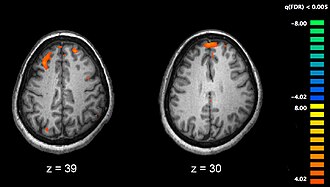

Shizofrenija je povezana s finim promjenama u strukturi mozga, pronađenim u 40 do 50% slučajeva, te neurokemijskim procesima tijekom aktunih psihotičnih stanja.[3] Istraživanja koja su koristila neurofiziološke testove te tehnologiju za slikovni prikaz mozga poput funkcionalne magnetske rezonancije (fMRI) i pozitronske emisijske tomografije (PET) za istraživanje funkcionalnih razlika u moždanoj aktivnosti, pokazala su da se razlike najčešće javljaju u frontalnom režnju, hipokampusu i temporalnom režnju.[54] Smanjenje volumena mozga, manje od onog u Alzheimerovoj bolesti, pronađeno je u dijelovima frontalne moždane kore i temporalnih režnjeva. Nije poznato jesu li ove volumetrijske promjene progresivne ili su postojale prije početka bolesti.[55] Ove razlike povezane su s neurokognitivnim deficitima često povezanim sa shizofrenijom.[56] Zbog promjena u neuronskim putevima, predloženo je da o shizofreniji treba razmišljati kao skupini neurorazvojnih poremećaja.[57]